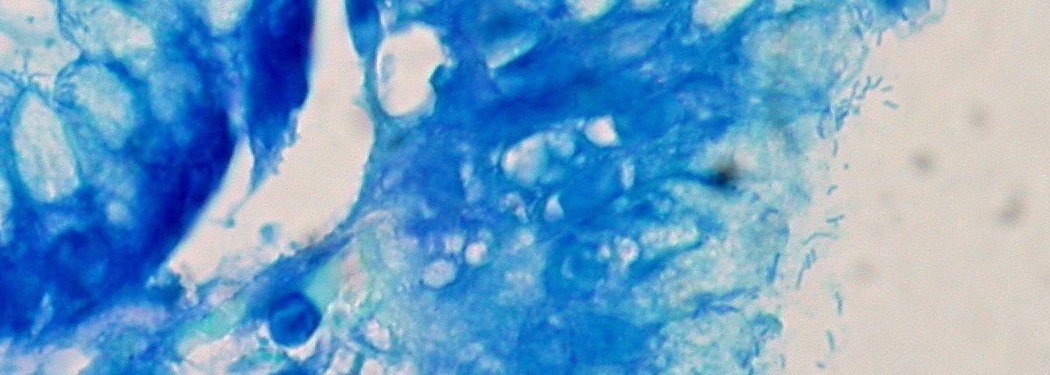

Certaines bactéries provoquent des cancers dans l’estomac, mais les préviennent dans l’œsophage. Nos microbes intestinaux sont garants d’équilibre, mais potentiellement mortels s’ils parviennent dans le sang. Ces exemples l’attestent : un germe n’est jamais « bon » ou « mauvais » par nature. Tout est affaire de contexte.

Moi, microbiote, maître du monde de Ed Yong, éditions Dunod, 2017